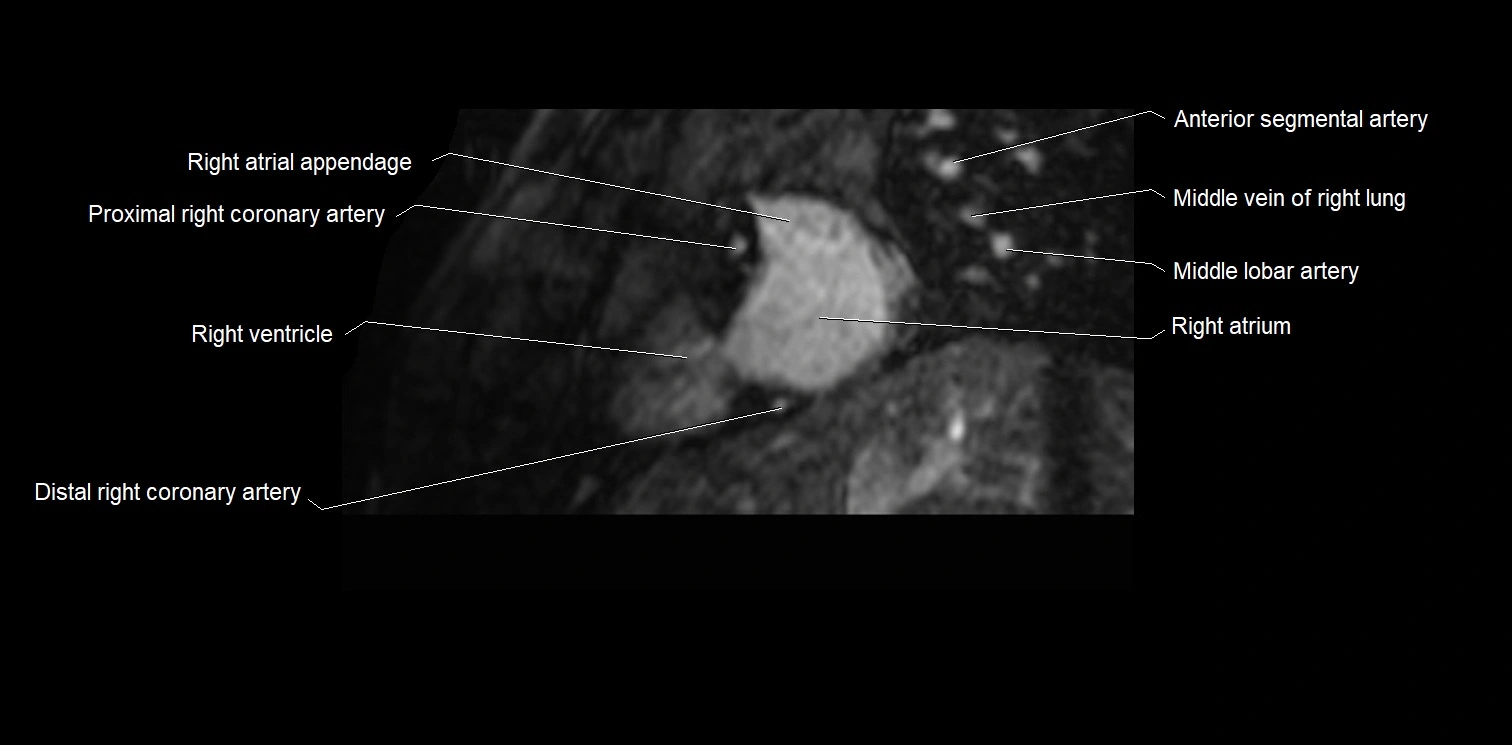

MRI image